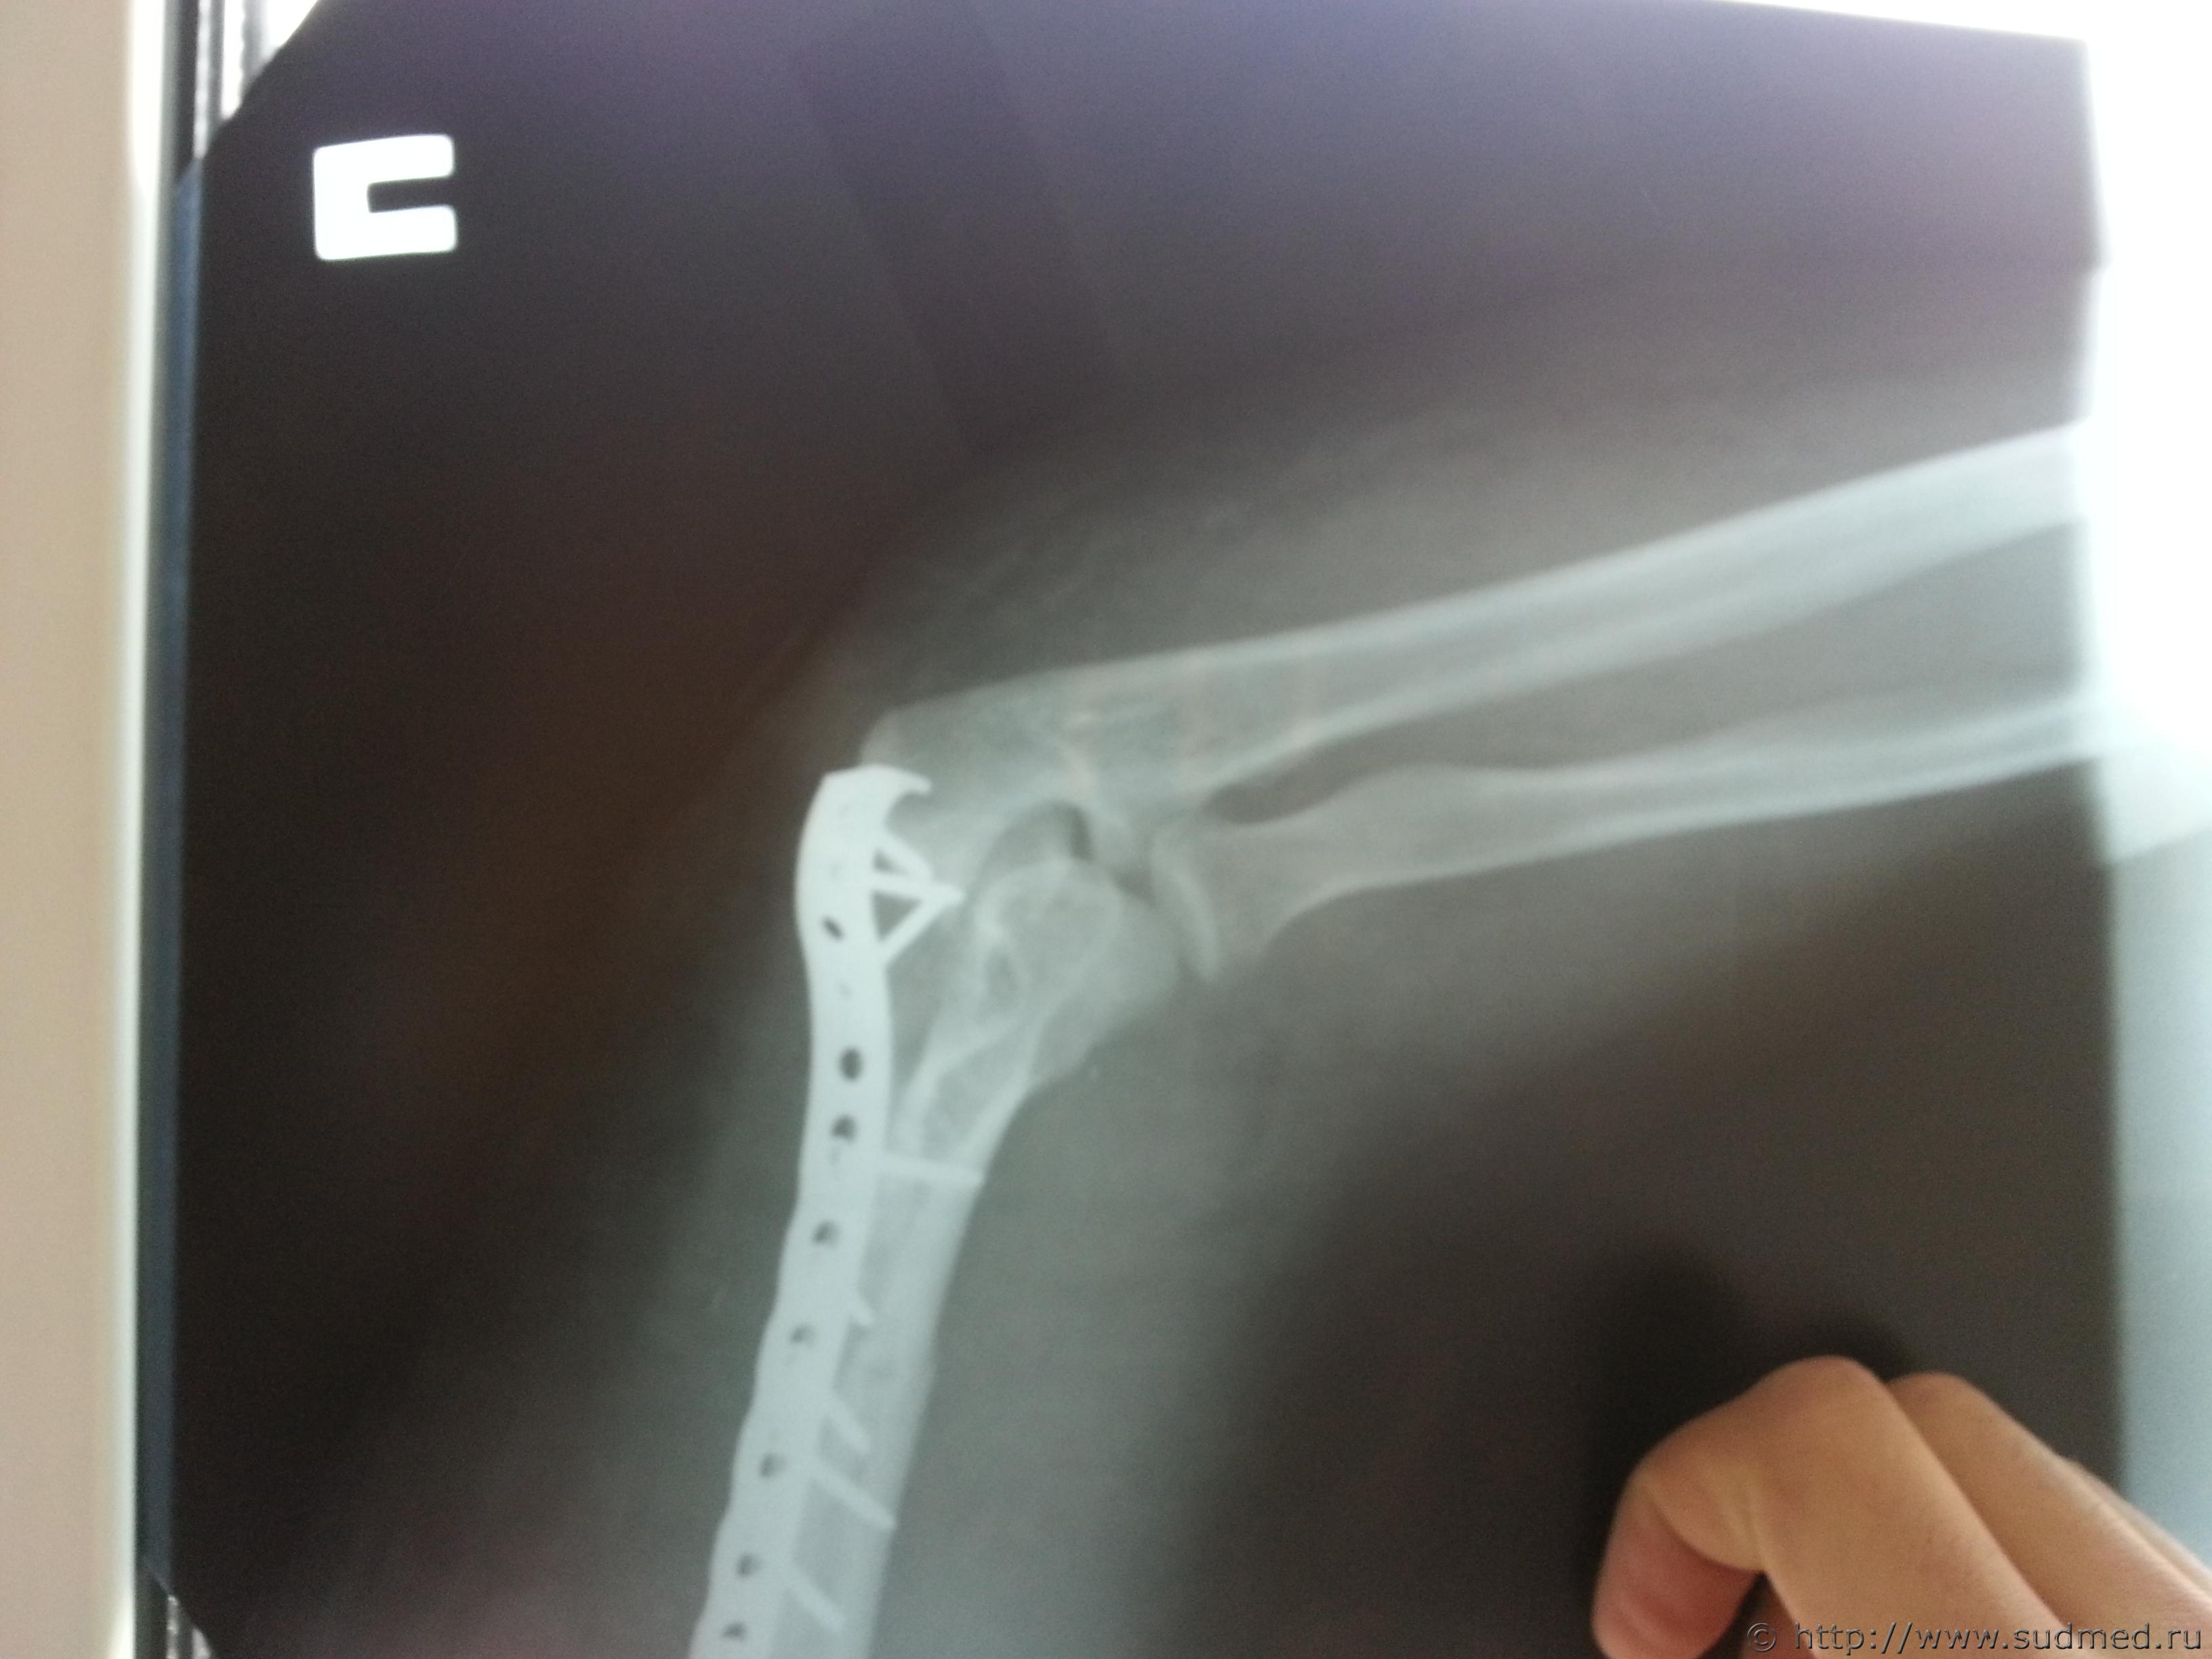

Винтообразный перелом нижней трети части плечеквой кости со смещением отломков, Винтообразный перелом механизм повреждения

Фото перелома до и после операции прилагаю

по первым сканам, что Вы выложили вряд ли можно что-то конкретное сказать, по последнеиу - искючать вариант перелома при обстоятельствах, изложенных в вопросе 1 не стал бы, и еще - место перелома не характерно для возникновения его при падении на вытянутую руку, перелом возможен без наружных повреждений, 4- вопрос не имеет судебно-медицинской составляющей и отношения к экспертам и вообще не знаю кто на такие вопросы может отвечать..кроме шаманов

Согласен с Gladius, место перелома не характерно для падения на руку, а характер перелома по снимкам похож на "винтообразный", по механизму образования как раз типичный для "выкручивания" руки. К сожалению, качество цифровых изображений не позволяет высказаться с уверенностью. Возможно, при изучении оригиналов снимков эксперт сможет сказать больше.